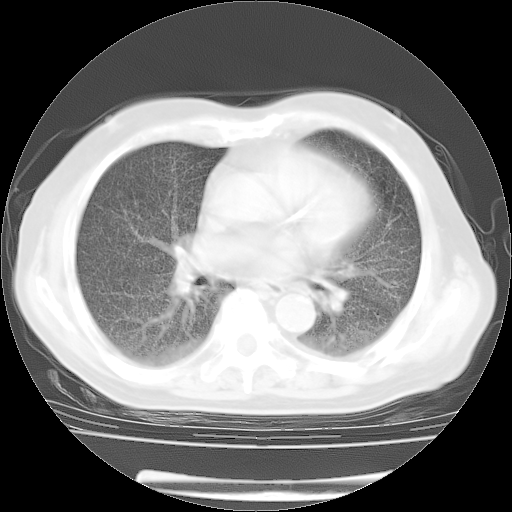

4月14日肺部CT

楼主| 发表于 2010-4-28 16:51 | 显示全部楼层

楼主| 发表于 2010-4-28 16:53 | 显示全部楼层

肺部CT平扫未见异常。